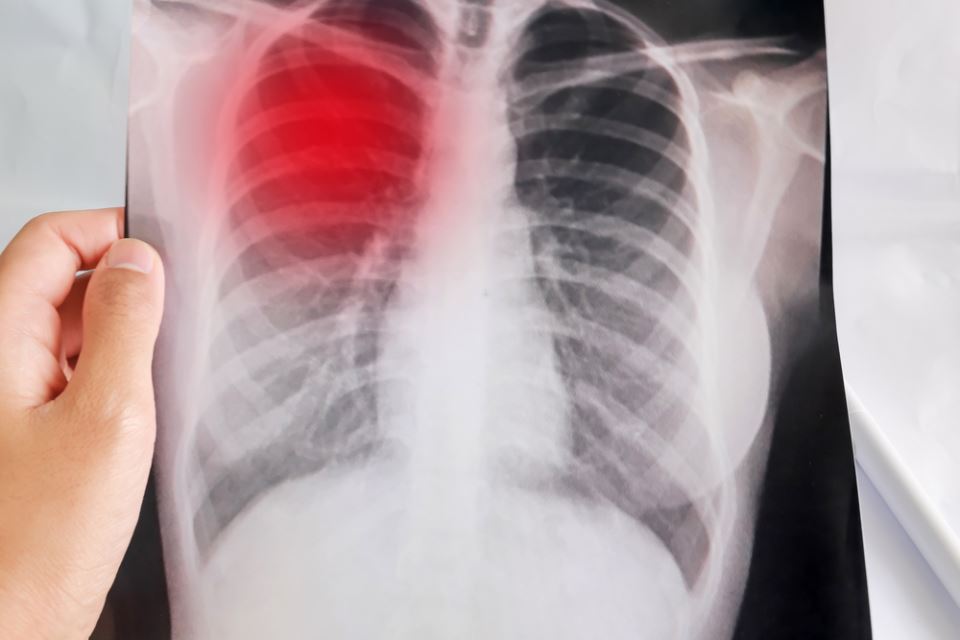

Големата кашлица е вид респираторна инфекција која во најголем број случаи ја предизвикува бактеријата "Bordetella pertussis". Постојат повеќе фактори или предизвикувачи кои можат да доведат до нејзина појава, меѓу кои се:

Преносот се врши преку капки, а просечниот период на инкубација изнесува околу десет дена. Заразноста се намалува со текот на времето, а најголема е кон крајот на инкубацијата. Големата кашлица спаѓа во сезонски инфекции и почеста е во летниот период, иако може да се појави во текот на целата година. Протективниот ефект се состои во тоа што телото на овој начин се обидува да го „исфрли“, односно елиминира потенцијалниот извор на инфекција, сигнализирајќи дека нешто се случува во организмот.

Дијагнозата се потврдува врз основа на присуството на бактеријата "Bordetella pertussis" и "PCR" тест. Се проверува и нивото на "IgM" и "IgA" антитела, додека бројот на леукоцити и лимфоцити е зголемен, што укажува на борба на организмот со инфекцијата.

Големата кашлица се лекува со пропишување антибиотици доколку станува збор за бактериска инфекција, како и со антитусици и спазмолитици. Кај потешки форми понекогаш се применуваат и кортикостероиди. Ретко може да има потреба и од кислородна терапија.

Дополнителни симптоми се недостаток или прекини на доток на воздух во белите дробови (апнеа), како и сина боја на кожата (цијаноза).